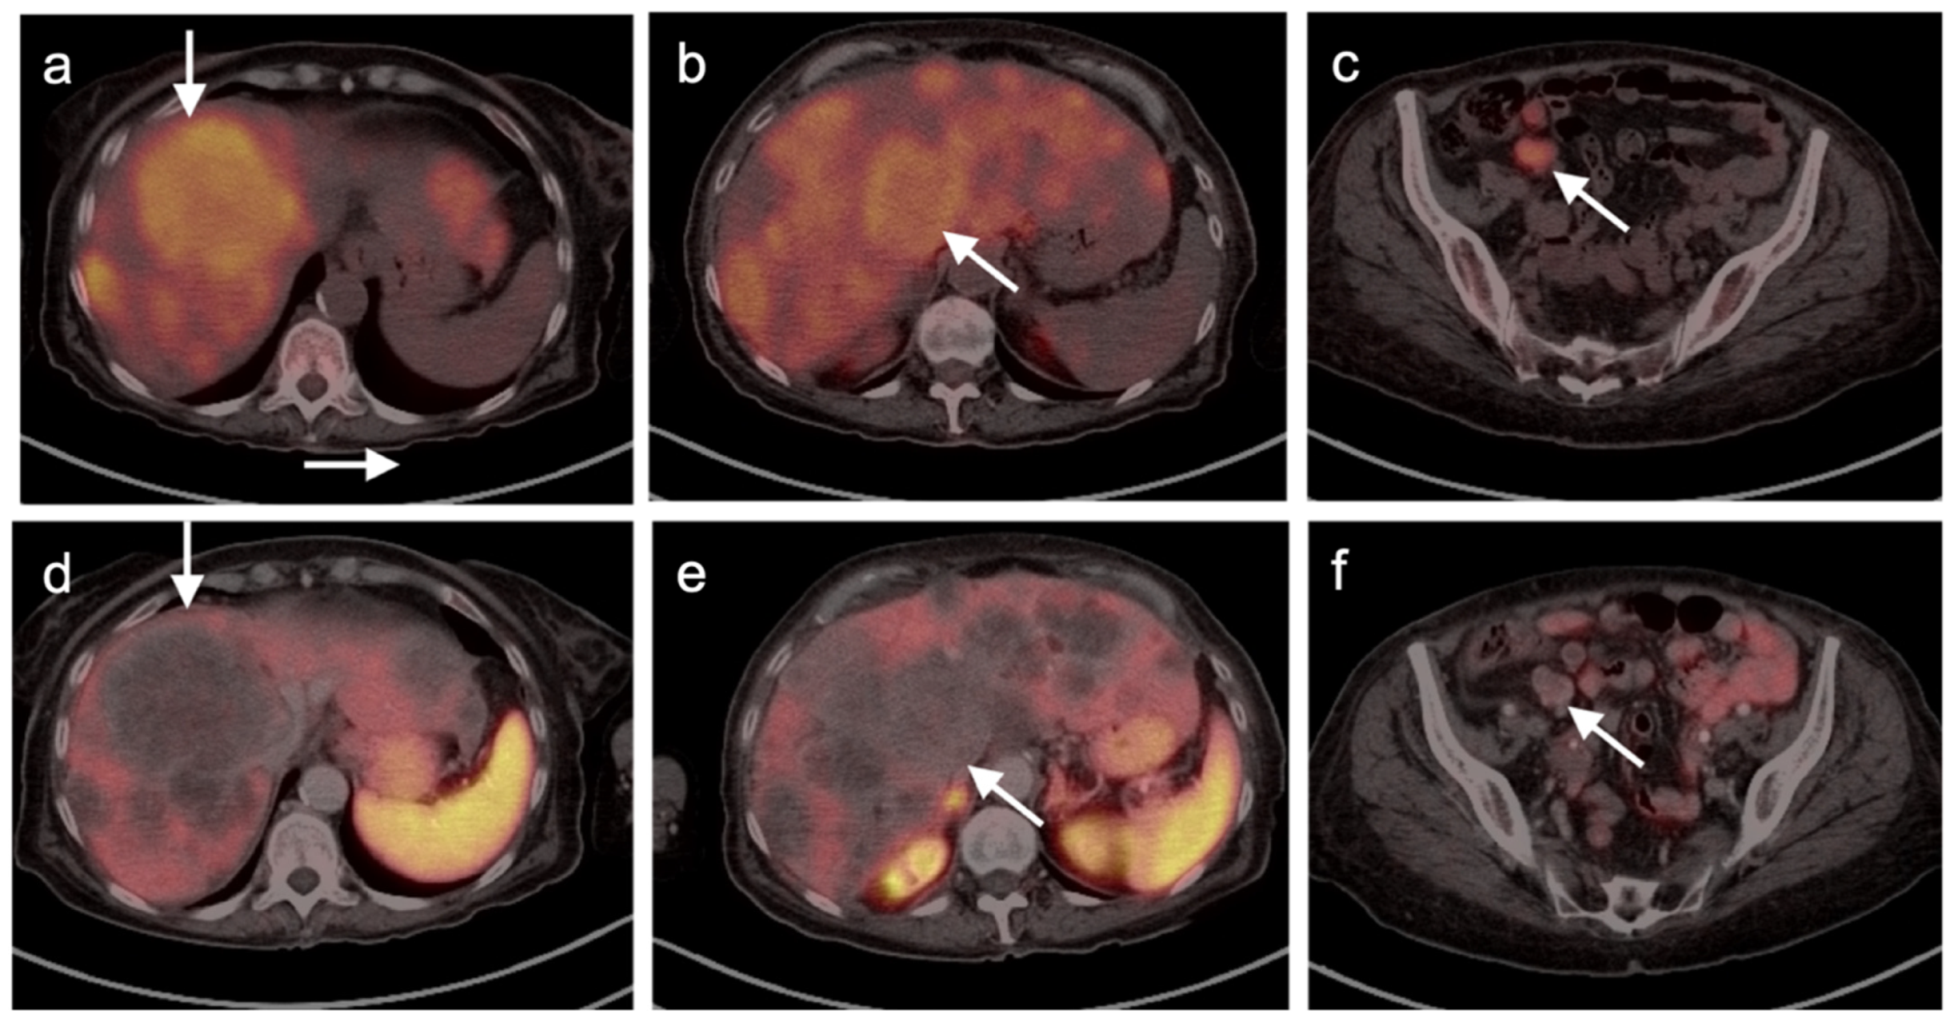

2.3.3. Mucosal Melanoma